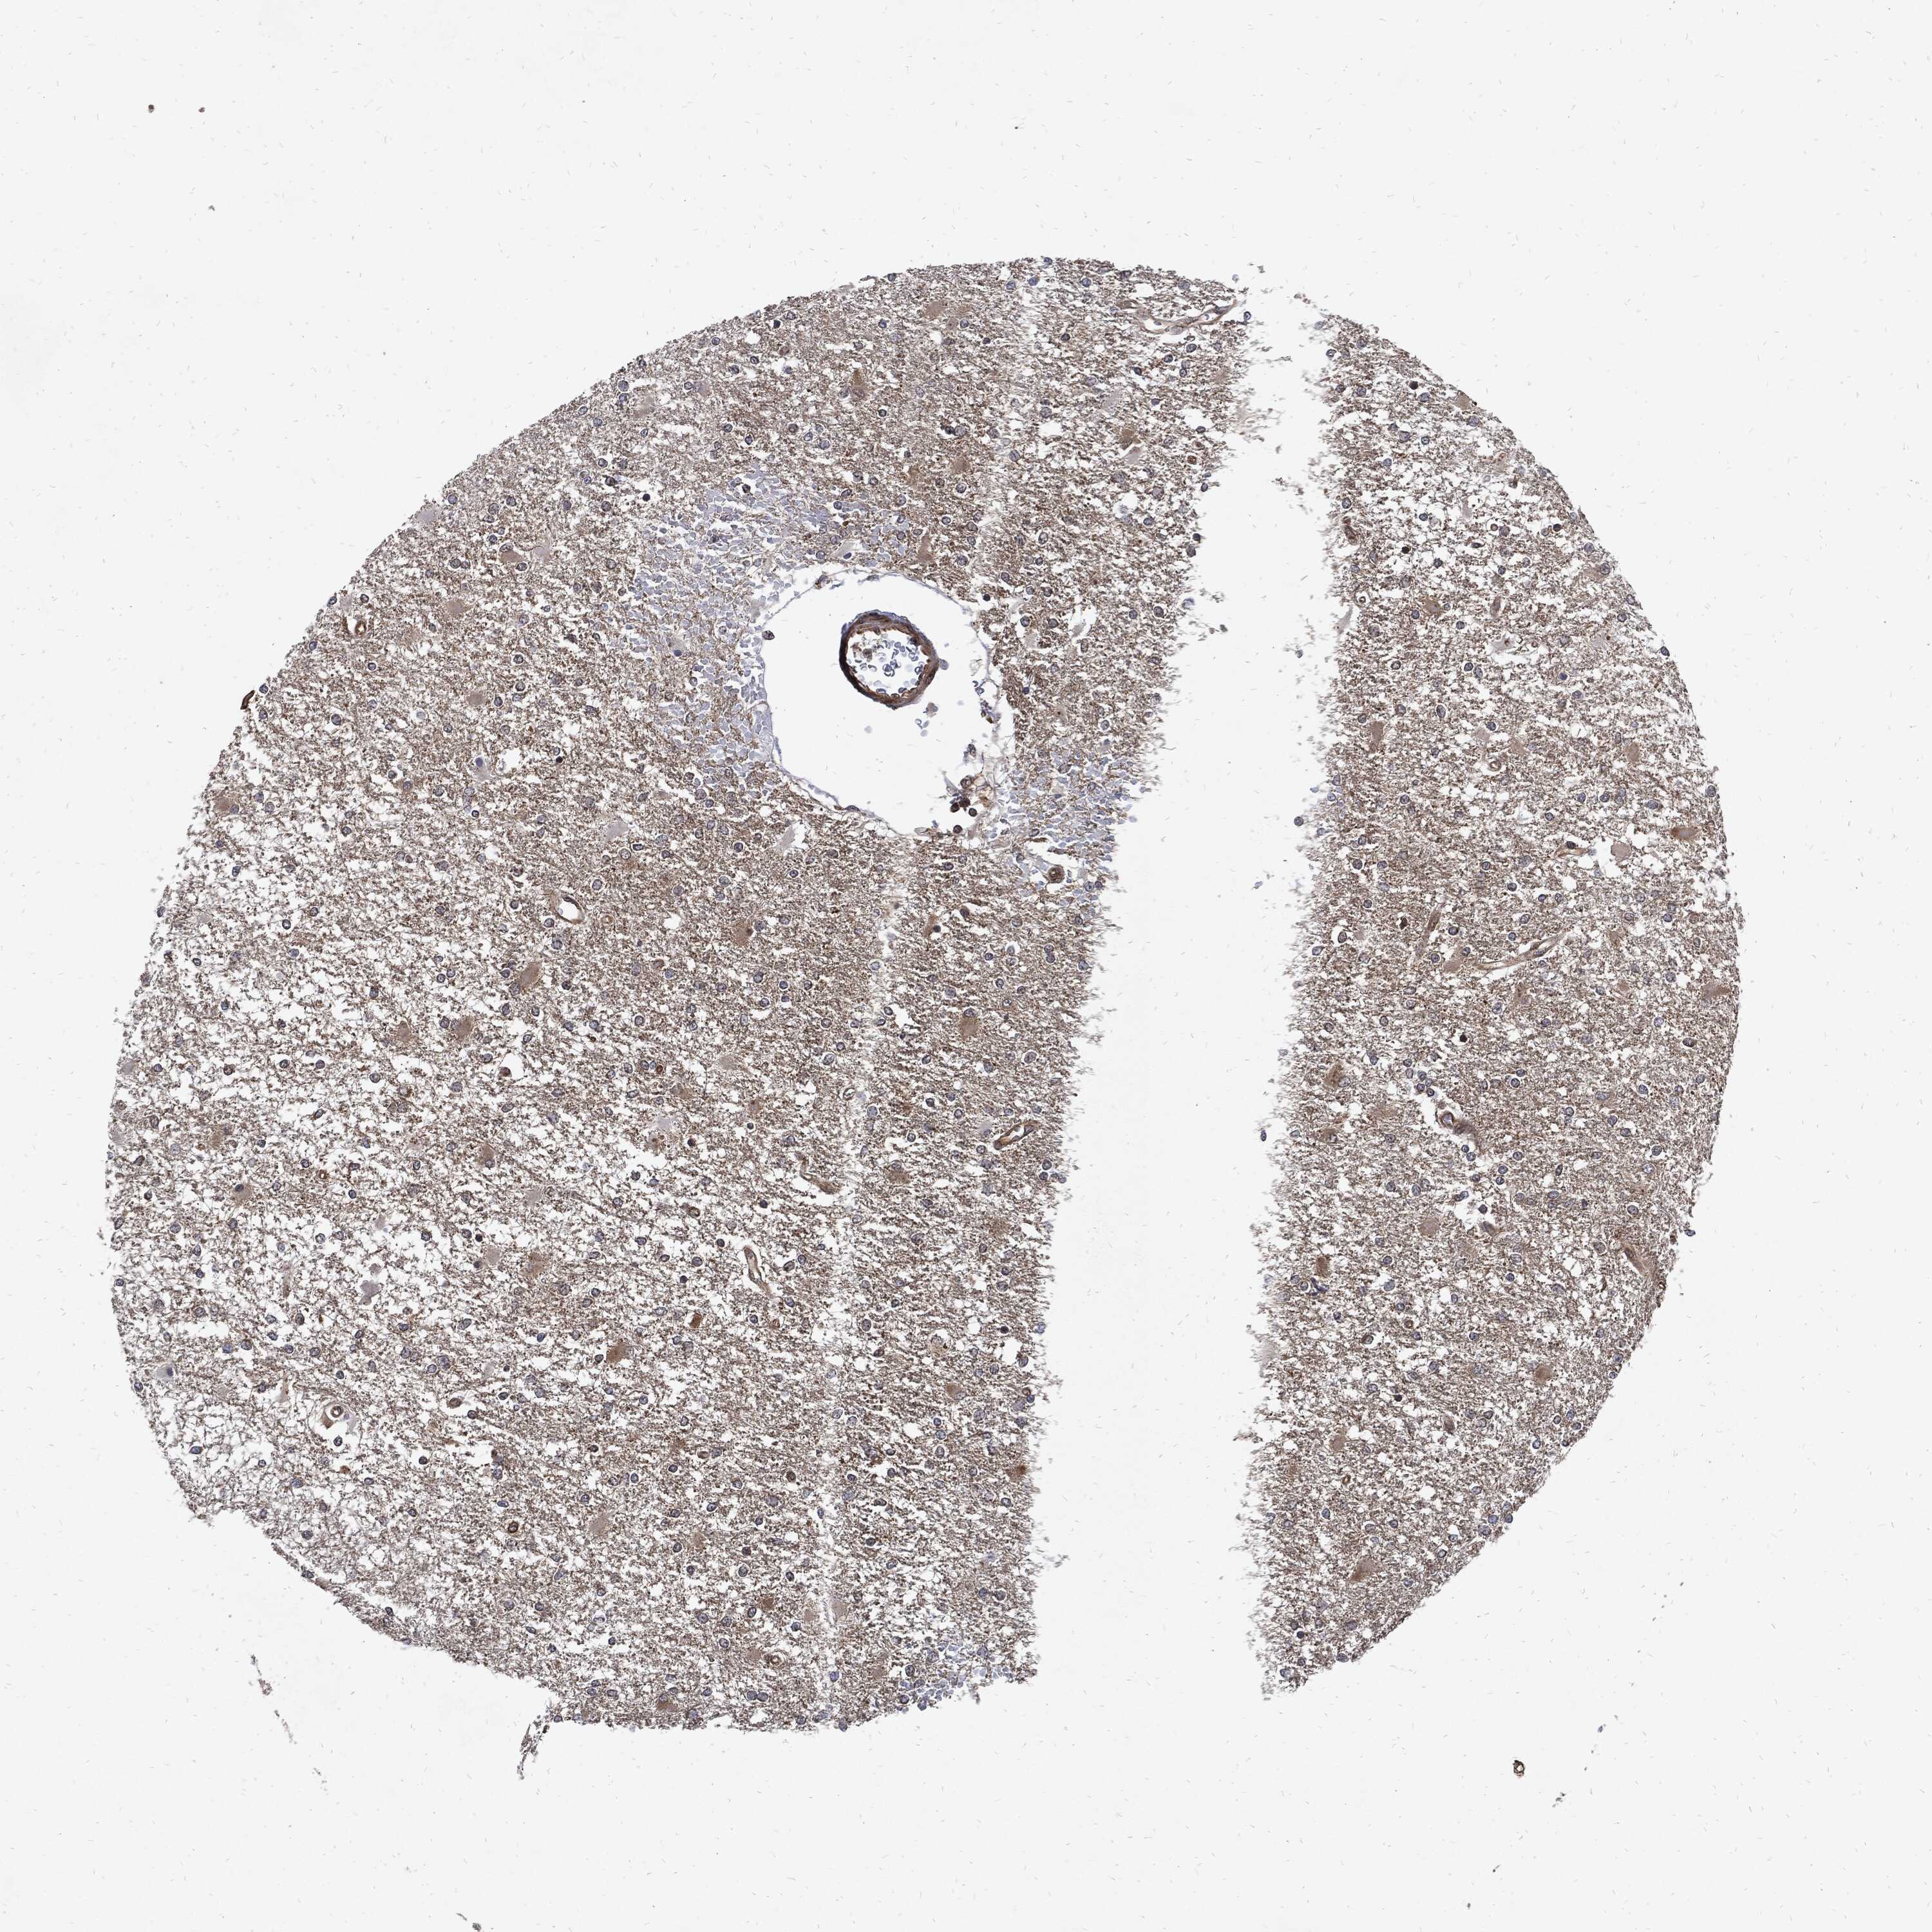

GLIOMA - Protein expressioni

A mouse-over function shows sample information and annotation data. Click on an image to view it in a full screen mode. Samples can be filtered based on level of antibody staining by selecting one or several of the following categories: high, medium, low and not detected. The assay and annotation is described here.

Note that samples used for immunohistochemistry by the Human Protein Atlas do not correspond to samples in the TCGA dataset.

Antibody stainingi

Antibody staining in the annotated cell types in the current human tissue is reported as not detected, low, medium, or high, based on conventional immunohistochemistry profiling in selected tissues. This score is based on the combination of the staining intensity and fraction of stained cells.

Each image is clickable and will lead to virtual microscopy that enables deeper exploration of all samples and also displays staining intensity scores, fraction scores and subcellular localization as well as patient and tissue information for each sample.

Antibody HPA034635

Antibody HPA069977

Antibody HPA071875

Antibody CAB009108

Staining

High

Medium

Low

Not detected

Intensity

Strong

Moderate

Weak

Negative

Quantity

>75%

75%-25%

<25%

None

Location

Nuclear

Cytoplasmic/membranous

Cytoplasmic/membranous,nuclear

Glioma, malignant, Low grade

Glioma, malignant, High grade